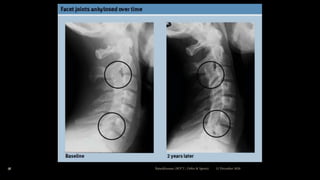

Radiographic features

 Sacroiliac joint –

 Erosion & sclerosis of bone near the articular

surface

 Ankylos later

 Spine –

 Apophyseal joint erosion

 Squaring of the vertebral bodies with ossification of

disc margins

 Syndesmophytes

 “Bamboo Spine” due to calcification of longitudinal12 December 2020Ratankhuman (M.P.T., Ortho & Sports)

Radiology cont...

 Vertebral column often shows –

 Bony sclerosis with squaring of vertebral bodies

 Ossification of annulus fibrosis with syndesmophytes.

 This might lead to fusion of vertebral column with a classical

“Bamboo Spine”.

 Involvement of hip & shoulder joints –

 Joint space narrowing can be detected by conventional X-rays.

12 December 2020Ratankhuman (M.P.T., Ortho & Sports)